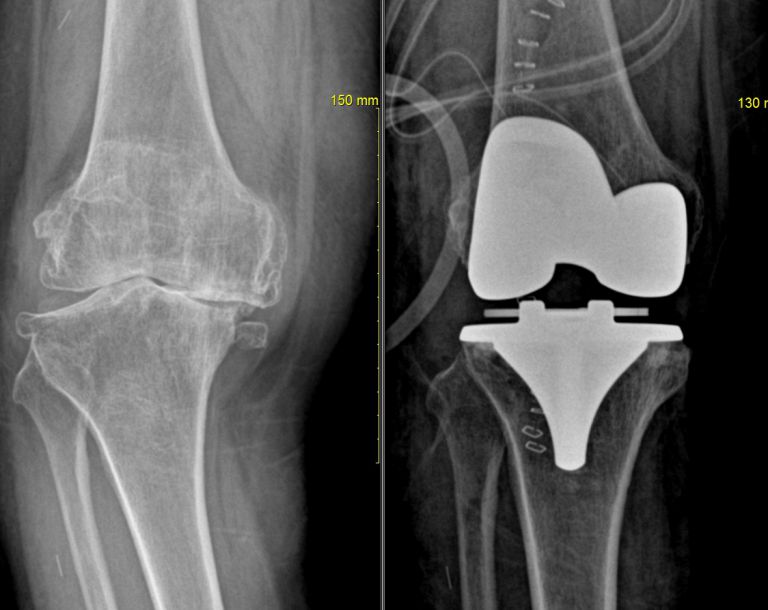

무릎 인공 관절

관리자

| 2008.10.22

| 1809